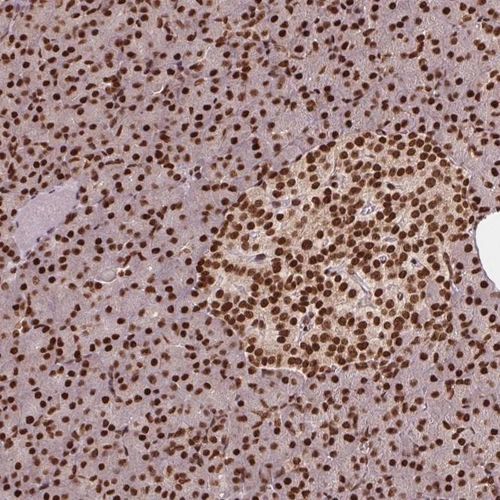

Immunohistochemical staining of human pancreas shows strong nuclear positivity in exocrine glandular cells and islets of Langerhans.